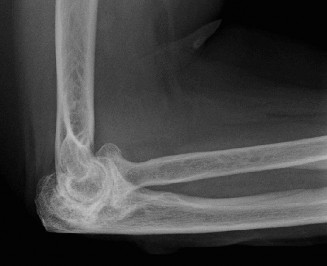

The patient undergoes resection arthroplasty with antibiotic cement spacer and a 6-week course of IV antibiotics. He returns to clinic 4 months later with improved pain, CRP <3, however, on examination he has a positive belly press sign and increased external rotation compared with the contralateral shoulder. Imaging is shown in Figure 2–57.

Figure 2–57

The correct answer is (D). The patient has completed his course of antibiotics and his spacer and is now an appropriate candidate for explanation of the cement spacer with revision shoulder arthroplasty, therefore Choices A and C are incorrect. The patient’s clinical examination findings point to rotator cuff tear (specifically subscapularis) which has occurred in the interval between his obtaining his initial total shoulder arthroplasty and his current examination. Therefore, total shoulder arthroplasty (Choice B) is contraindicated, and the patient should have a reverse total shoulder arthroplasty. Objectives: Did you learn...? Recognize the clinical presentation of a patient with infection after total shoulder arthroplasty?